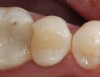

Replacement of existing restorations is responsible for 75% of all operative dentistry.15,19 The reasons for placement and replacement of restorations of direct restorative materials include: primary caries (Figure 1 and Figure 2); recurrent caries (Figure 3); poor margins (Figure 4 and Figure 5); restoration fracture (Figure 6 and Figure 7); tooth fracture (Figure 8); esthetics (Figure 9); non-carious tooth structure lost (attrition, abrasion, abfraction, erosion) (Figure 10); and pain/sensitivity.

Figure 1  Initial caries. Class V carious lesions.

Figure 1